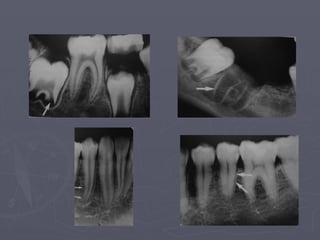

Mandibular canal

► It is a dark linear shadow with thin radiopaque

superior and inferior borders.

► Sometimes the borders are seen only partially

or not at all.

► The relationship of the canal to the roots of

the lower teeth may vary.

► If projected over the root apices, the lamina

dura will be overexposed and misinterpretation may

occur.